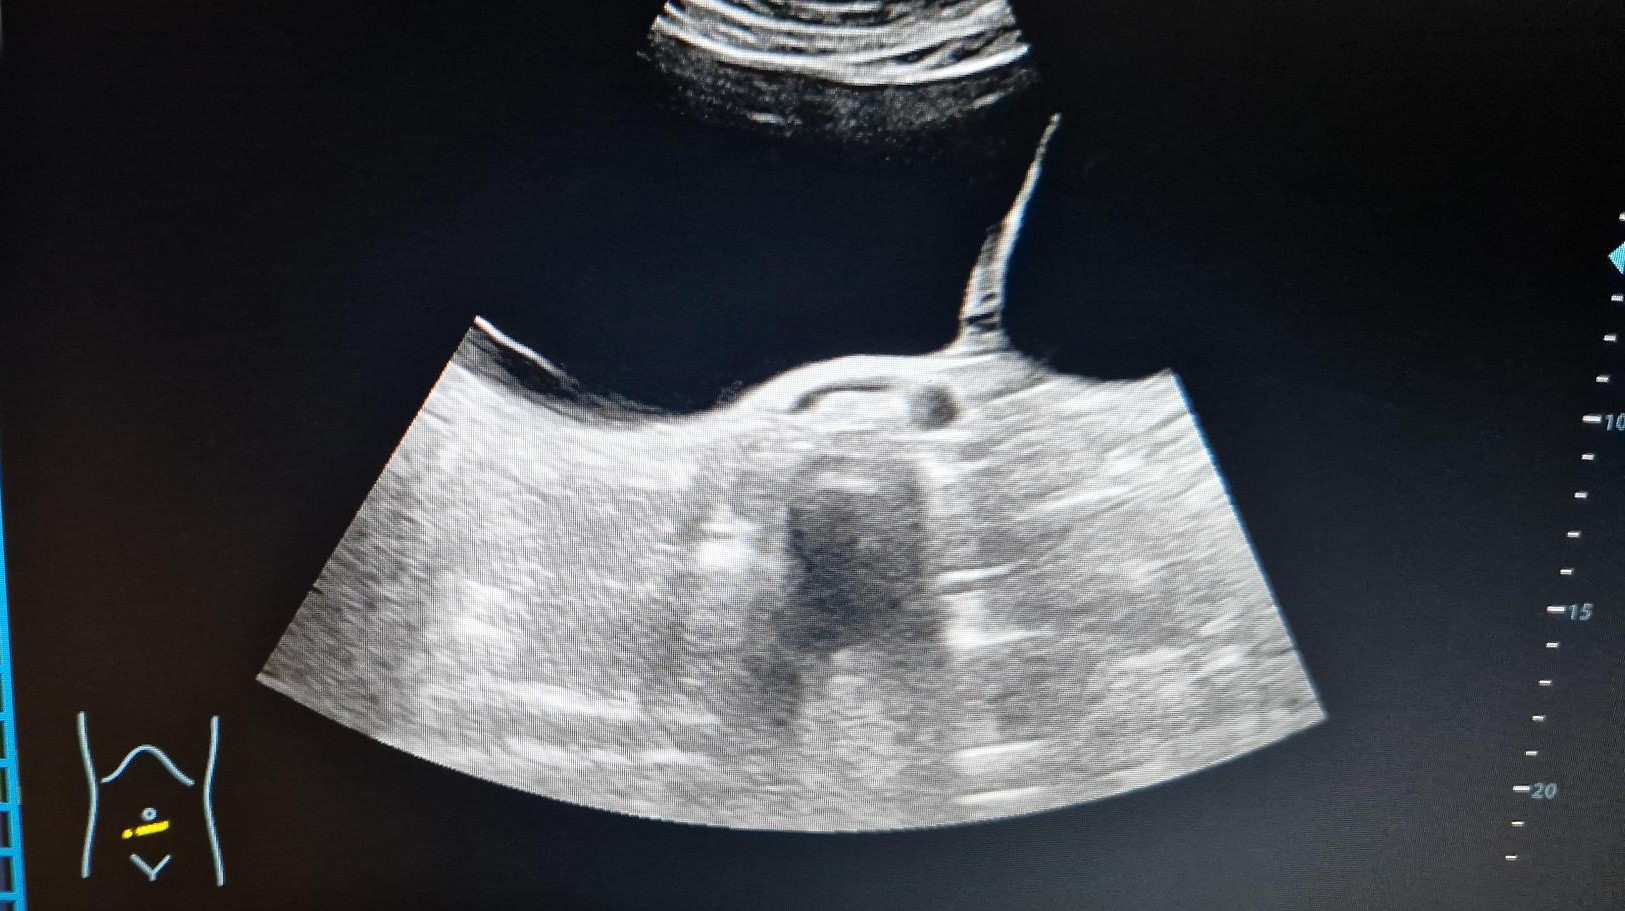

Eco abdomen: Masa anecoica con refuerzo posterior de gran tamaño con particulas en su interior, multilobulada y con tabiques en su interior que ocupa desde epigastrio, desplazando al páncreas, hasta mesogastrio, fosas ilíacas e hipogastrio, muy difícil determinar las medidas.

Informe Eco TV: útero en AV con endometrio de aspecto glandulo quístico de 9,6 mm (impresiona de pólipo endometrial). Douglas y ambas regiones anexiales ocupadas por formación quística de gran tamaño (280 x 93 x 190 de lateralidad no determinable) no abarcable en su totalidad ni con sonda abdominal. Dicha formación es multilobular, con tabiques de grosor variable (el mayor de 6 mm) vascularizados sin papilas, de cápsula regular y fina en porción más próxima a ambas fosas ilíacas. No líquido libre.